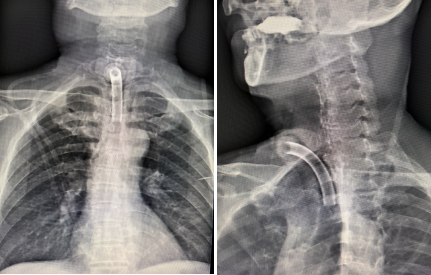

近日,我院耳鼻咽喉-头颈外科刘吉峰副主任医师团队成功为一位喉癌侵犯环后区及食道入口的患者实施了全喉切除术、下咽部分切除术、永久性气管造瘘术、双颈淋巴结清扫术及股前外侧游离皮瓣移植...